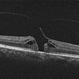

- macular hole, hole closed, post-op

- Macular hole post op, hole closed, 20/30.